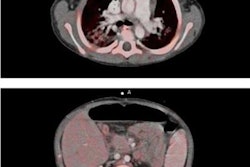

"What we suggest is to introduce MDCT as a global diagnostic investigation to assess both the coronary arteries and cardiac function," said Silvestri, adding that this study focused on the critical topic of MDCT in LV functional assessment. "We compared MDCT with echo and cardiac magnetic resonance (CMR) -- that is the gold standard technique. All techniques were performed on the same day within a very short temporal window to avoid bias due to hemodynamic and functional changes."

The study included 16 heart-transplant patients with normal sinus rhythm who underwent 64-detector-row retrospective ECG-gated MDCT (LightSpeed VCT, GE Healthcare) with tube current modulation, comparing the results to CMR (1.5-tesla scanner, 8-16 short-axis steady-state free-precession images) and echocardiography (3 mHz probe, apical view measurements). All exams were performed on the same day for each patient.

Two expert readers blinded to the results of other modalities independently evaluated LV function at MDCT in terms of ejection fraction (EF), end-diastolic volume (EDV), end-systolic volume (ESV), stroke volume (SV), cardiac output (CO), and mass of the left ventriculum using dedicated software on a workstation (TeraRecon), comparing the results to CMR and echocardiography. MDCT interobserver agreement was measured and heart rate was measured during all of the exams, and no beta-blockers were used.